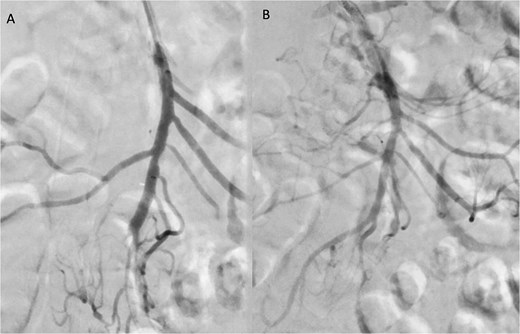

A 76-year-old female patient with a medical history of diabetes mellitus and cholecystectomy presented to the emergency department with a 7-month history of postprandial abdominal pain, food fear, and weight loss (25–30 kg). Over the past 3 days she referred symptom worsening to constant pain. On the physical examination, the abdomen was tender to palpation. Laboratory results revealed leukocytosis (13.700/μl), high C-reactive protein (23 mg/dl) and lactate 0.7 mmol/L. A previously performed computed tomography angiography (CTA) in context of a lithiasic cholecystitis revealed celiac trunk occlusion and pre-occlusive stenosis of the SMA ostium but the patient was not referred for a vascular surgery consultation. A CTA scan obtained in the emergency department revealed thrombotic occlusion of the SMA origin associated with distal embolization (Fig. 1A–C). In this context, the diagnosis of acute-on-chronic mesenteric ischemia was assumed, and the patient was proposed for urgent endovascular revascularization. A 7F (French) sheath was placed via percutaneous access in the left brachial artery, and SMA catheterization was performed using a triaxial system (sheath, MP catheter and Progreat® catheter). Diagnostic angiography confirmed the CT findings (Fig. 2A). Catheter-directed thrombolysis was first performed with a 5 ml bolus of alteplase, followed by percutaneous thrombectomy using the Penumbra® system (Fig. 2B), with retrieval of fresh thrombus (Fig. 3). Primary stenting of the SMA ostium was also performed using an Advanta® 6 × 39 mm stent with proximal flair, with an excellent imagological result (Fig. 4A and B). The postoperative course was uneventful, with significant improvement of symptoms and clinical status. A CTA prior to discharge revealed a patent stent with proper placement and no evidence of residual thrombus (Fig. 5A and B). The patient was discharged on the seventh postoperative day with apixaban 5 mg twice daily. Follow-up of the patient at 6 months revealed that the stent remained patent, with no reported abdominal complaints. The patient gained 15 kg at this point of follow-up.

Angiographic images before (A) and after (B) thrombectomy of the superior mesenteric artery (SMA).